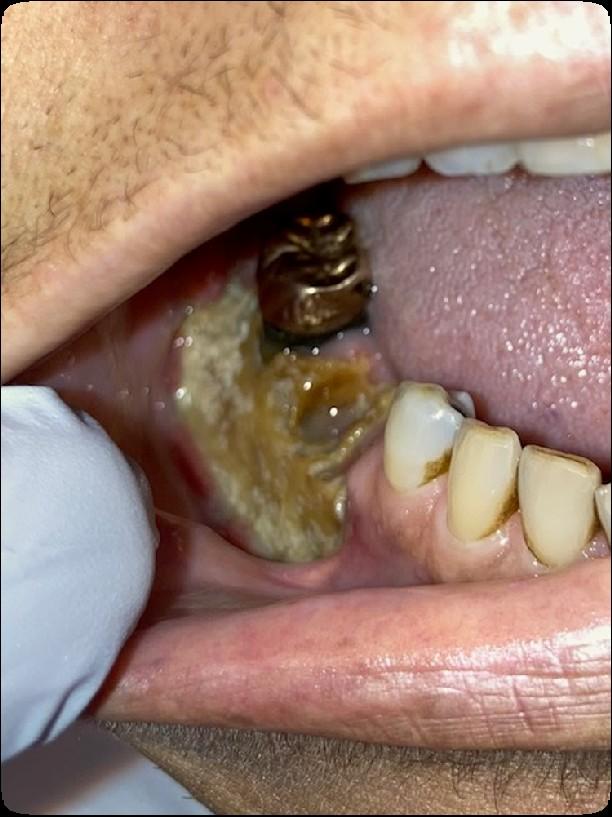

Osteonecrosis of the Jaw

MRONJ: Medication Related Osteonecrosis of the Jaw

• Rare oral side effect called osteonecrosis of the jaw that is associated with certain medications, bone-modifying agents.

• Osteonecrosis of the jaw is a condition where small area(s) of the jawbone have difficulty healing and the bone starts to breakdown and die.

How Common is MRONJ?

The risk is thought to be less than 1% for patients taking IV bonemodifying agents, and at least ten times less likely than that for patients taking the drugs by mouth.

If I take these medications, am I automatically at risk?

• Anyone who takes these medications has a chance of developing ONJ.

• However, most reported cases occur after a type of oral “injury” – which could a tooth extraction, chronic periodontal (gum) disease, an oral surgical procedure, or simply a nonhealing traumatic ulceration.

• Tobacco use, treatment with corticosteroids, long-term use of bonemodifying agents, and diabetes also may increase the risk of this condition occurring.

What are the signs of MRONJ?

• The hallmarks of ONJ are exposed bone or gum/mucosa/tissue wounds that heal very slowly or do not heal at all for eight weeks or more after an injury to the mouth.

• Some patients report that this begins with a feeling of “roughness” on the gum tissue. If these open wounds become infected, there may be pus or swelling in the adjacent gum tissue.

• Many times, this condition is painless in the beginning, and patients only experience pain after the exposed bone becomes infected.

How is MRONJ treated?

• Education

• Careful oral hygiene

• Conservative interventions

• Avoid surgical intervention, if possible

• PATIENCE!